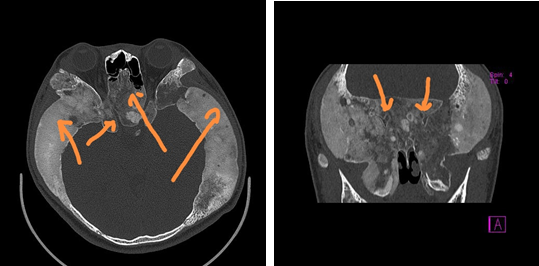

△患儿术前颅脑CT扫描显示,整个颅骨:

据吴文灿教授团队涂云海副主任医师介绍,骨质纤维异常增生症很罕见,是一种病因不明、缓慢进展的骨纤维组织疾病。正常骨组织被吸收,而代之以均质梭形细胞的纤维组织和发育不良的网状骨骨小梁,可能系网状骨未成熟期骨成熟停滞或构成骨的间质分化不良所致。对于颅骨异常增殖者,过度增生的骨质将压迫视神经导致视力下降,甚至完全丧失。以往对该类疾病没有任何方法,甚至只能眼睁睁地看着患者视力完全丧失。但自从2015年开始,吴文灿教授突破了此极限,在国际上率先采用导航引导进行内窥镜下视神经减压术与颅底重建术,手术效果很好,且迄今为止,为60多例患者成功施行了手术。

吴文灿教授说,张同学不同于以往的同类患者,一方面,他整个鼻腔鼻窦、颅底的过度增生的骨质已经部分囊性变,像泥巴一样软,在去除骨质时根本找不到以前那种感觉,且很难精准定位,稍有不慎,就会引起视神经医源性创伤,甚至损伤海绵窦或颈内动脉而大出血,危及生命;另一方面是,因为囊性病,囊腔内充满了大量的血管,血供非常丰富,术中出血很厉害,而此种出血因为是异常的骨纤维中的血管出血,一般的止血措施都不管用,为手术带来了极大的困难。同时,因为头部特别大,从鼻外至颅底的距离比其他患者长的多,操作相当困难,甚至医院手术室的剥离子、钳子等的长度都不够。好在步步为营,一点一点地把异常的骨质纤维去除,最终非常完美地完成了该手术。